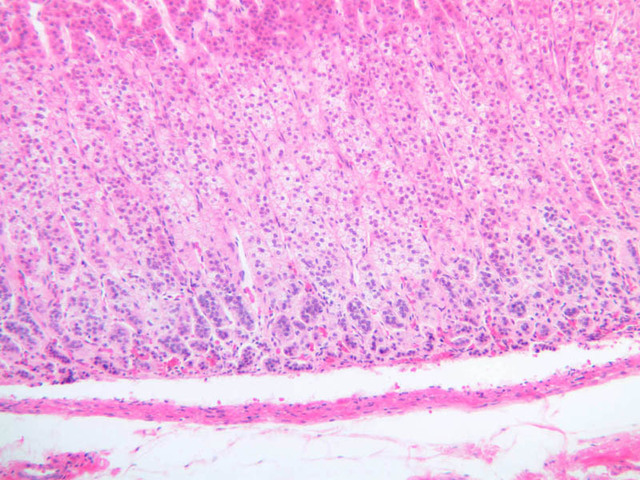

Examine slide B-56 (H&E [2.5x, 10x, 20x, 40x-labeled] [10x, 20x, 40x-labeled] [20x, 40x] [10x, 20x, 40x-labeled] [10x, 20x, 40x]). The connective tissue capsule of each parathyroid gland is continuous with that of the thyroid gland. It extends into the substance of the gland, dividing it into poorly defined lobules. Fat cells may separate the groups of cells and increase with age. Note the rich capillary network. The parenchyma is composed of two types of cells: (1) Principal or chief cells and (2) oxyphil cells. The polygonal chief cell is by far the more numerous cell type. Its nucleus is centrally located and has a vesicular chromatin pattern with a prominent nucleolus and its cytoplasm stains rather lightly. Oxyphil cells, which are less regular in shape and considerably larger than chief cells, are scattered singly or in small clusters. Their nuclei are smaller and more condensed than those of the chief cells and, owing to a very rich complement of mitochondria, their cytoplasm is distinctly acidophilic.